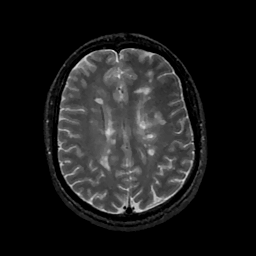

MR Study #11, May 5, 1991 -- Slice #33

[Home][Help][Clinical][Tour 1][Tour 2] Slice 33